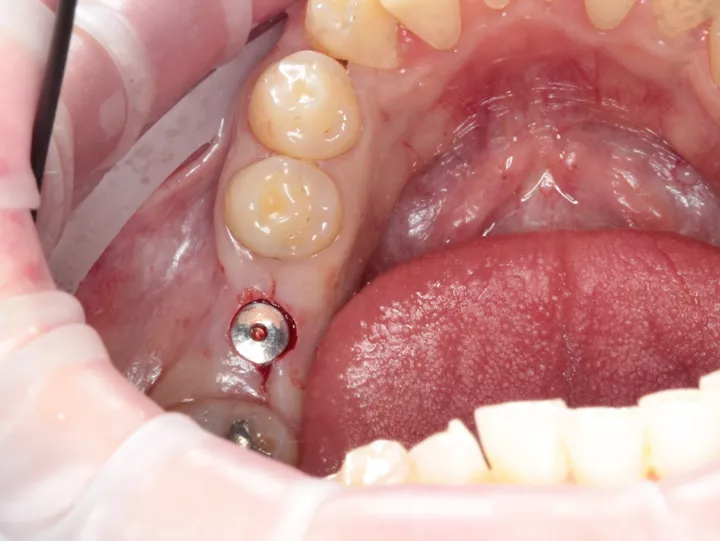

9a. 9b. 9c. Dans ce cas, en raison de la quantité suffisante d'os, j'ai pu utiliser l'approche sans lambeau avec le tissue punch.

10. Ensuite, j'ai suivi le protocole de forage Anthogyr Axiom X3® pour l'os de type 2 (sous-préparation  d'un foret). L'implant a été placé à travers le guide. Le couple a atteint 50 N.cm. L'ensemble de la procédure nous a pris environ 20 minutes !

11. La vis de couverture doit être serrée à la main.